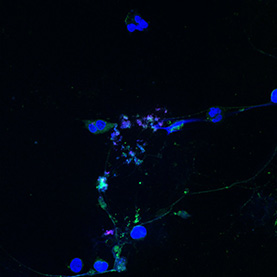

Many processes within the body are changed by the presence of cancer. These images show the response of microglia, immune defense cells in the brain, to cancer cells. When microglia encounter glioblastoma multiforme, one of the most aggressive brain cancers, they shift from a relaxed, elongated shape to a rounded, ready-for-combat conformation.

These images echo the work of Anna Atkins, a British botanist and photographer who used a contact printing technique called cyanotyping to capture the form of plants and algae. Emily Chen’s work similarly seeks to explore biological function, in this case the immune response to brain cancer, by capturing and comparing biological forms.